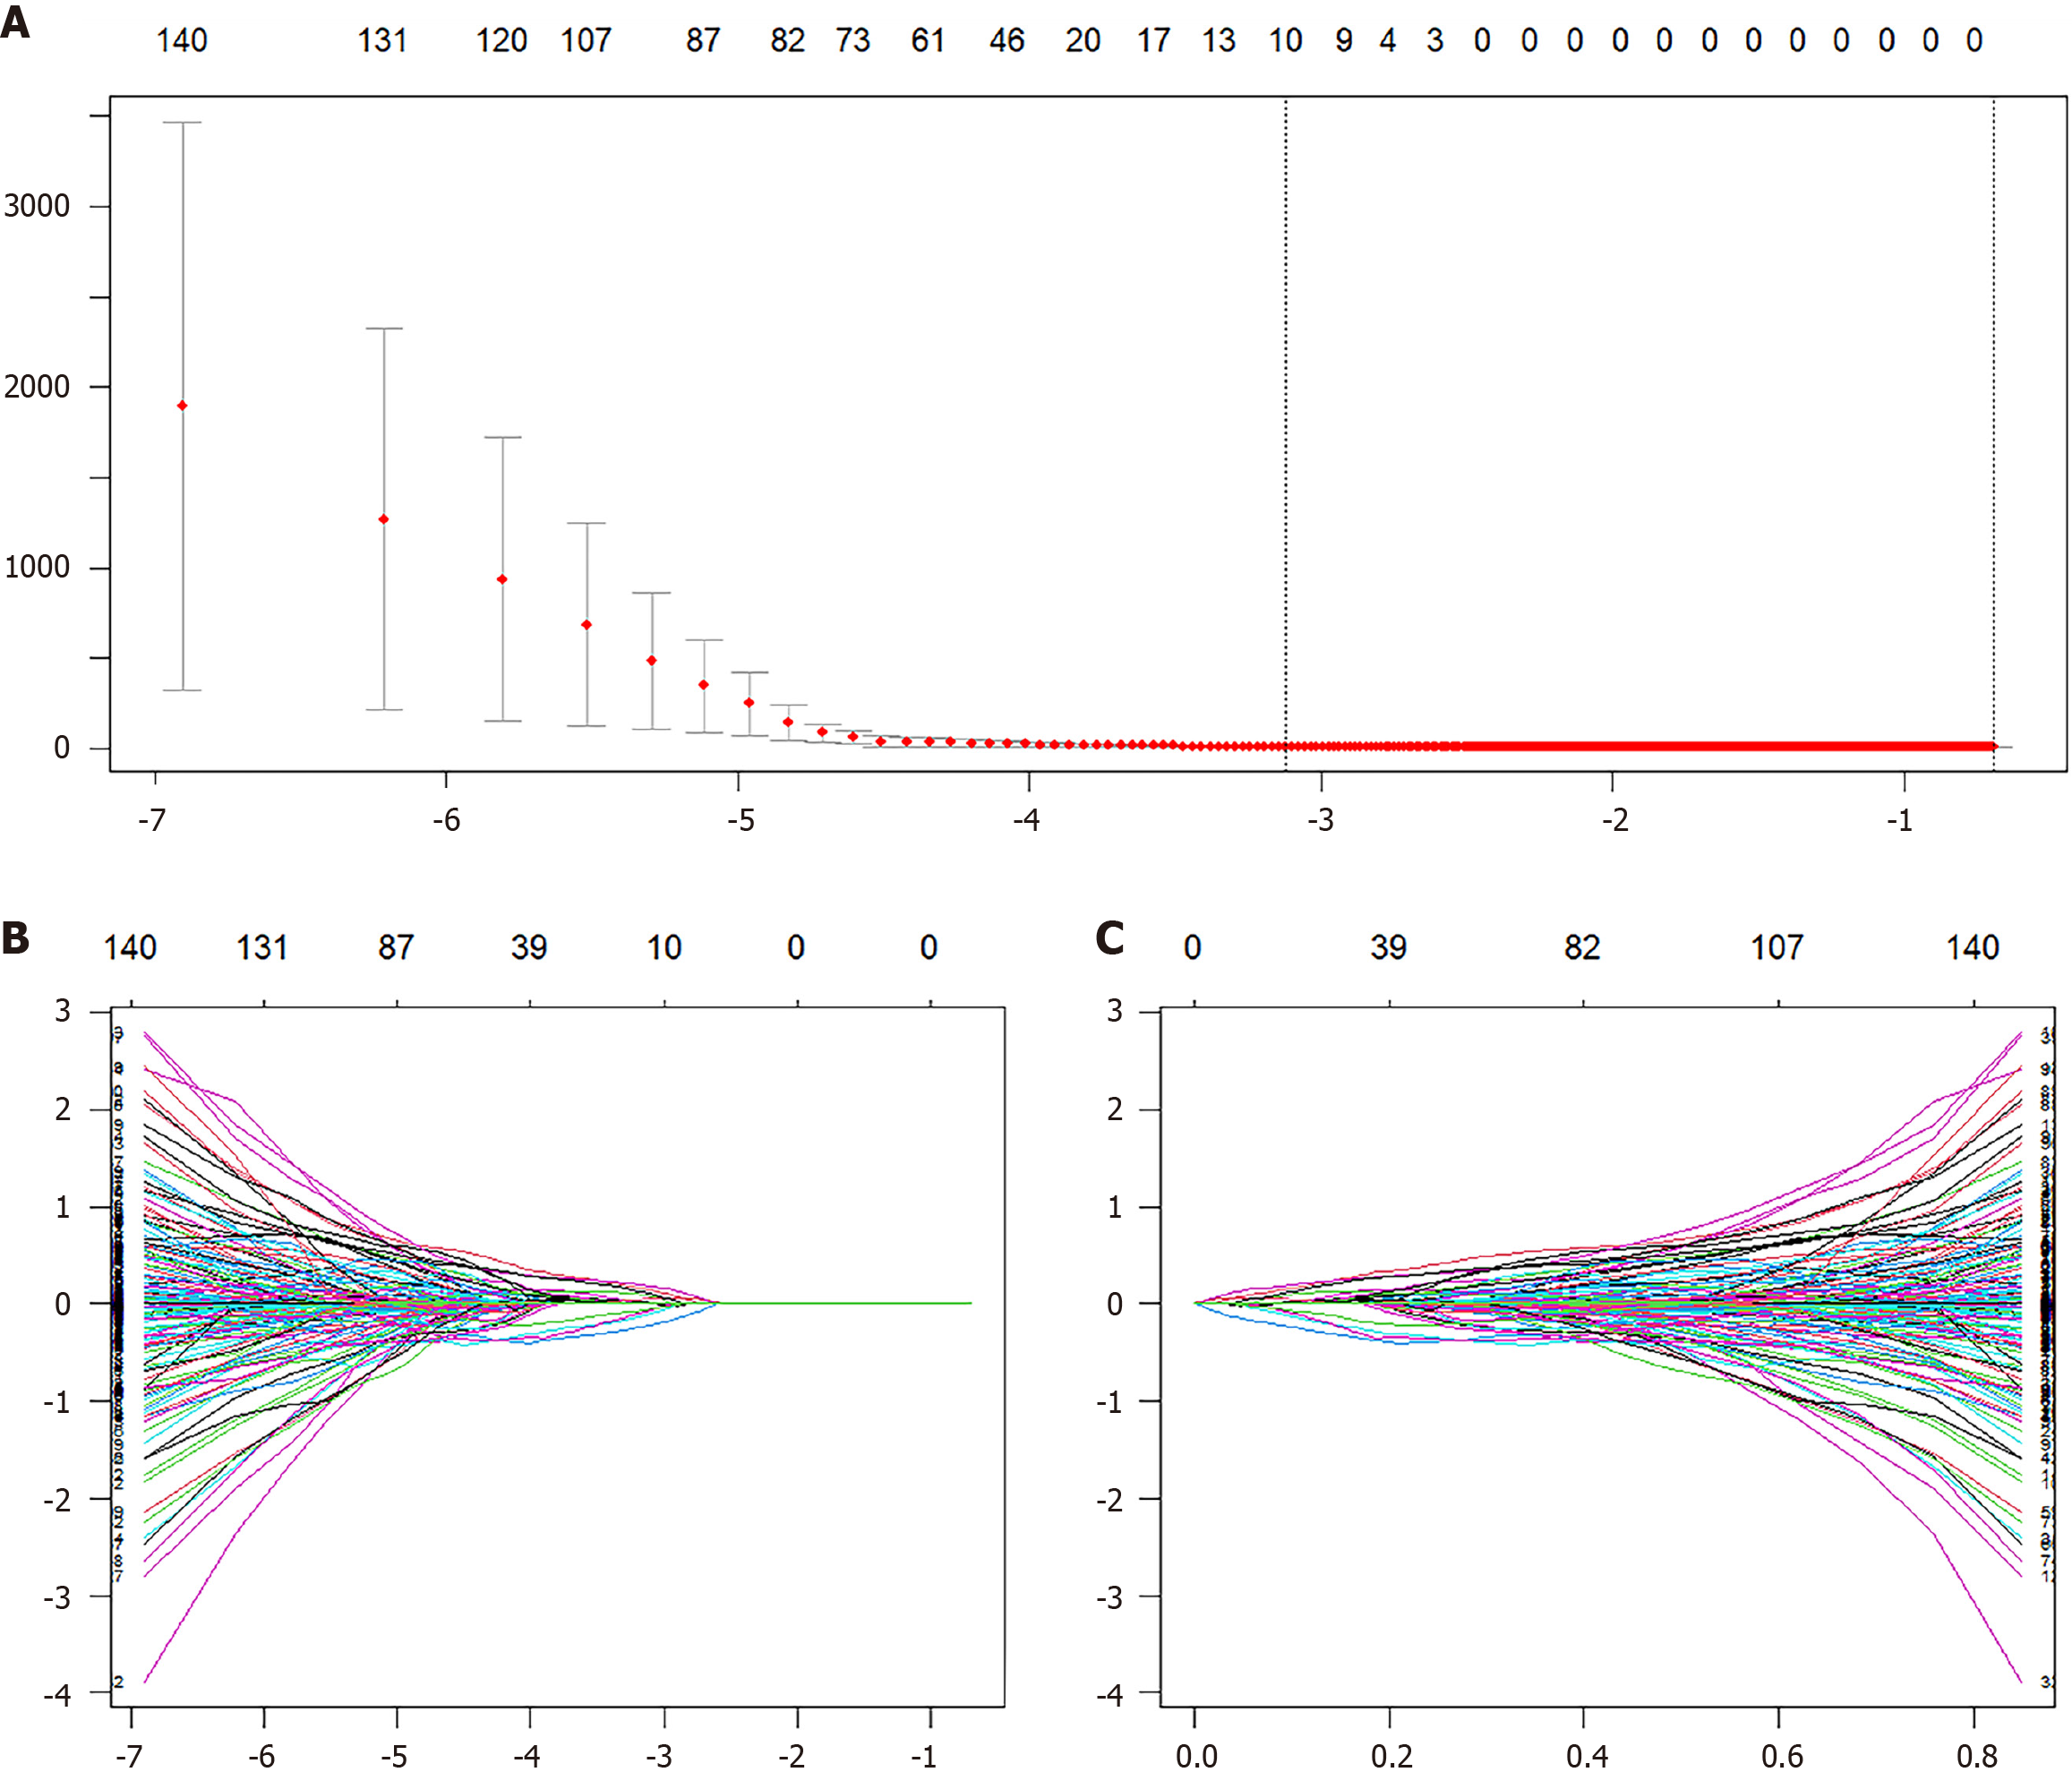

A total of 1702 radiomic features were extracted per patient, with 851 features from each ROI. To ensure data stability, reliability was assessed by computing the ICC for a randomly selected subset of 30 patients. Features with ICC > 0.75 were retained, resulting in 1333 reliable radiomic features for subsequent analysis. Feature selection was performed using LASSO Cox regression with 10-fold cross-validation to optimize the penalty parameter (λ), which identified 10 nonzero radiomic features for constructing the Radscore (Figure 3). These features included nine wavelet-transformed texture features and one GLCM-derived feature, reflecting their relevance in capturing multi-scale texture patterns and texture coarseness (Supplementary Table 1). Univariate Cox regression analysis of clinical variables revealed significant associations with sex, portal vein thrombosis, invasive treatment to relieve hepatic venous outflow obstruction, use of anticoagulant medication, ascites, spleen thickness, red blood cell count, hemoglobin level, platelet count, serum sodium level, creatinine level, AST level, alkaline phosphatase level, albumin level, direct bilirubin level, prothrombin time, BCS type, and Child-Turcotte-Pugh class. Multivariate Cox regression further identified three independent risk factors for GEV bleeding in BCS patients. Invasive treatment to relieve hepatic venous outflow obstruction, use of anticoagulant medication and hemoglobin levels (Table 3). These variables were used to construct a clinical-only risk prediction model (C model), which demonstrated significant predictive performance.